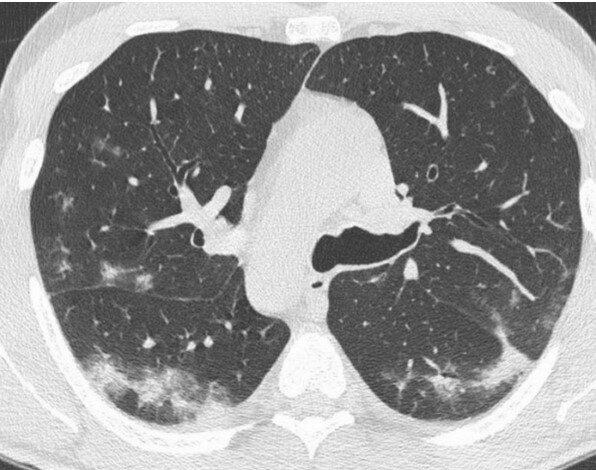

Шаг 2: Сканирование Проведите сканирование легких с уверенностью и мастерством. Изучите каждый слой тканей, каждый уголок легочных долей, ищите признаки патологии как следует. Пневмония скрывается не всегда на поверхности, поэтому доверьтесь своим навыкам обнаружения.

Шаг 4: Внимание к деталям Дьявол кроется в деталях, и пневмония - не исключение. Обратите внимание на характерные признаки патологии: консолидации, пузырьковый знак, плевральные изменения. Только бдительность и душа исследователя помогут раскрыть все секреты пневмонии. Шаг 5: Интуиция Доверьтесь своей интуиции и объедините ее с знаниями. Иногда ответ может быть скрыт в самой глубине изображения, в натянутых линиях и тенях. Разгадка пневмонии требует синхронности разума и сердца, доверьтесь своей интуиции.